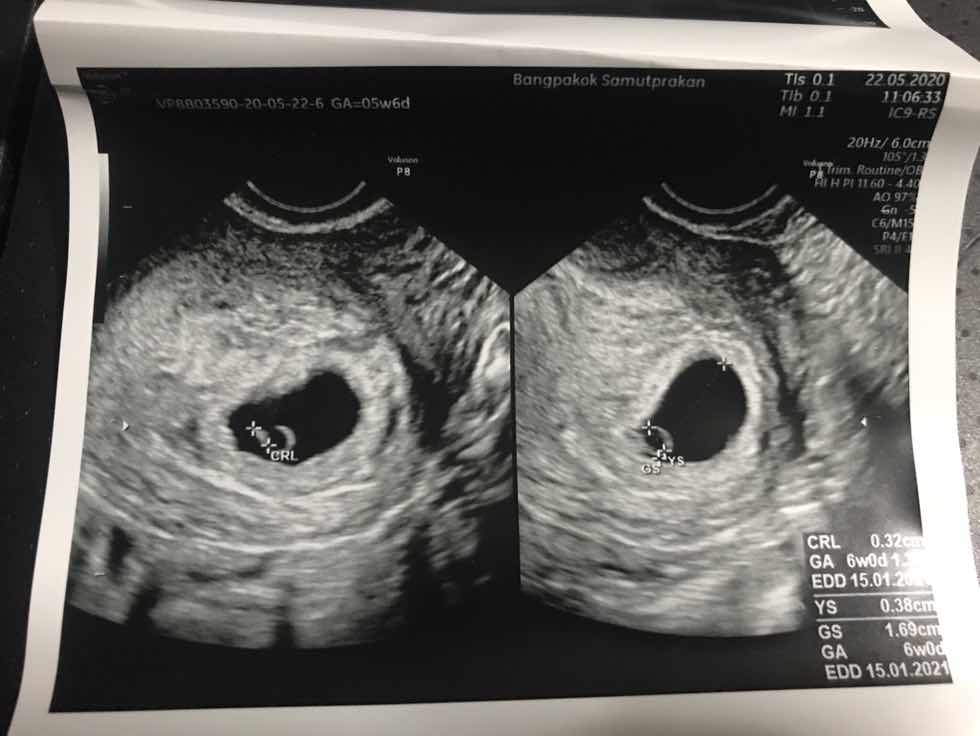

เพิ่งรู้ว่าท้องได้6W ก่อนหน้านั้นกินแอลกอฮอล์ พักผ่อนน้อย จะส่งผลต่อน้องมั้ย?

เราเพิ่งรู้ว่าตัวเองท้องได้6week ก่อนหน้านั้นเราทานไวน์ทุกวันเสาร์ ประมาณ1ขวด /เสาร์ มาโดยตลอด แถมได้รับสารเสพติดโดยบังเอิญอีกเนื่องจากเพื่อนใส่ยาอี ผสมลงในขวดไวน์ ซึ่งเราเพิ่งรู้เรื่อง ทำให้เรากังวลมาก ว่าจะมีผลต่อเด็กมั้ย ปรึกษาหมอมาเมื่อวาน หมอบอกตอนนี้ไม่สามารถบอกอะไรได้เพราะน้องยังเล็กเกินไปตรวจไม่ได้ จะตรวจได้ตอน5เดือน เรื่องยาถ้าไม่ได้ใช้ประจำหรือต่อเนื่องไม่น่ามีผลอะไร อาจทำให้น้องไฮเปอร์นิดๆ แต่เรื่องดื่มไวน์นั้น หมอบอกว่าเราดื่มเยอะอยู่เหมือนกัน ถ้าเรากังวลว่าน้องจะไม่สมบูรณ์อยากยุติให้ปรึกษารร.แพทย์ ศิริราช รามา จุฬา แต่ถ้าลองเสี่ยงก็ต้องรอน้อง5เดือน เราควรทำยังไง ถ้ารอ5เดือนแล้วไม่โอเค เราคงทำใจไม่ได้กว่านี้ แต่ถ้ายุติตอนนี้ แล้วน้องปกติดี ก็กลายเป็นว่าเราทำร้ายเค้า ตอนนี้เครียดมากค่ะ แถมการใช้ชีวิตก็นอนตี3-4 ตื่น9-10โมง บางวันก็นอนน้อย ทานอาหารก็เกือบบ่าย เราไม่ได้ทำสิ่งที่มีประโยชน์กับลูกเลย เราควรทำไงต่อคะ สับสน ร้องไห้ตลอดเลยค่ะ